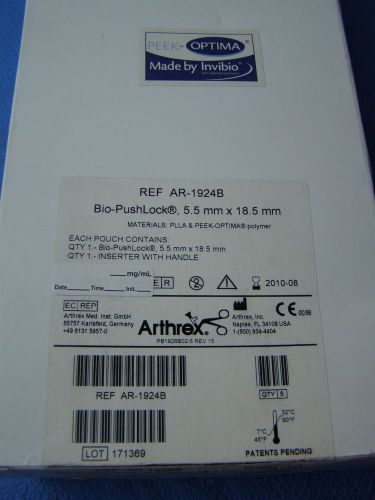

Box of 5 Arthrex Bio-PushLock 5.5mm x 18.5mm REF:AR-1924B